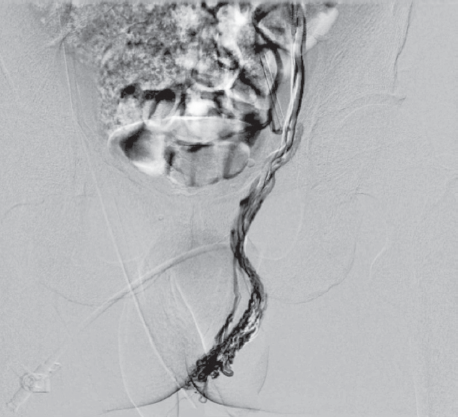

В 1987 г. G. Sigmund et al. на основании клинического осмотра, двунаправленного доплеровского ультразвукового исследования и ретроградной флебографии у пациентов с варикоцеле выделили два гемодинамических типа рефлюкса: stop-type, когда рефлюкс заблокирован компетентными клапанами яичковой вены, и shunt-type, когда рефлюкс распространяется из-за клапанной несостоятельности яичковой вены [11]. Данные G. Sigmund et al. (1987) легли в основу нашей флебографической классификации венной почечной гипертензии, которая предполагает два варианта в зависимости от степени декомпенсации клапанов левой яичковой вены (рис. 1).

Рис. 1. Варианты венной почечной гипертензии по данным рентгеноконтрастной ренофлебографии: a — рефлюкс в центральную вену левого надпочечника при отсутствии декомпенсации клапанного аппарата левой яичковой вены; b — рефлюкс в центральную вену левого надпочечника и в левую яичковую вену

Fig. 1. Variants of venous renal hypertension according to radiopaque renoflebography: a – reflux to the central vein of the left adrenal gland in the absence of decompensation of the valve apparatus of the left testicular vein; b – reflux into the central vein of the left adrenal gland and into the left testicular vein